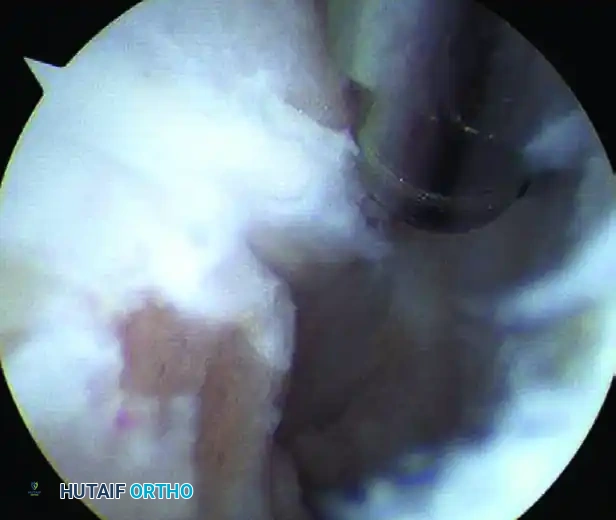

Image

FIGURE 50-14 Anterior subtalar débridement. A, Initial view obscured by dense synovitis. B, Visualization following aggressive synovial resection.

• Initial Debridement: After triangulation is achieved to place the working portals, the surgeon must blindly but carefully commence debridement using a 3.5 mm or 2.9 mm full-radius shaver. Continue this targeted debridement until the articular surfaces of the joint can be clearly visualized.

Upon initial entry into the subtalar joint, visualization is notoriously difficult. The arthroscope is often immediately confronted with a "red out" due to the dense, hypertrophic synovitis that fills the sinus tarsi.